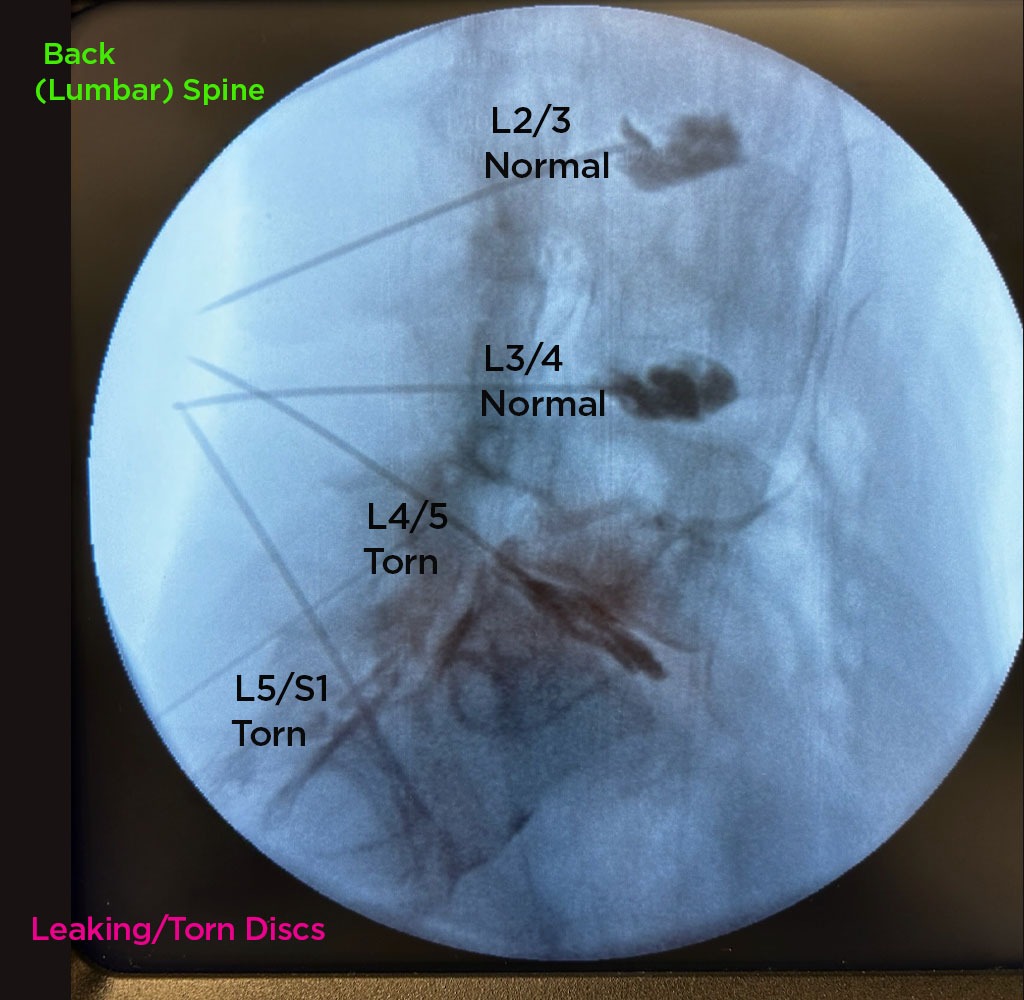

Annulargram™ Gallery

This gallery contains Annulargram images.

The Annulargram is a pain-free test and a crucial part of the DISCSEEL Procedure that identifies even the most subtle tears in spinal discs that MRI and discography cannot.

During the Annulargram, every disc in the region is tested to address current and future pain issues by finding even the most subtle annular tears. With the Annulargram, damaged spinal discs are pinpointed and precisely treated with Fibrin, leaving all healthy discs as they are.

Tears in spinal discs cannot be seen on MRI nor discography. As shown: leaky discs are only visible on the Annulargram.